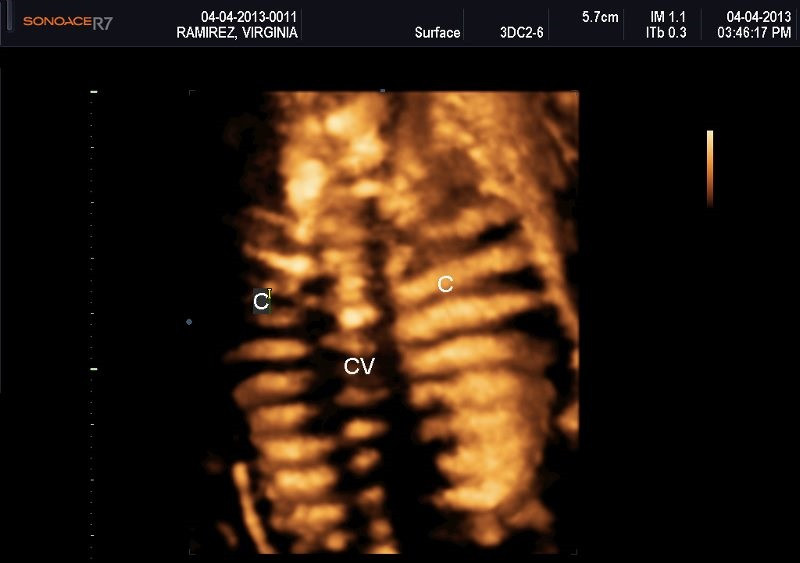

Varias ultrasonografías en 2D y 3D

Envíado por Dr. Nelson Menjívar Sarco